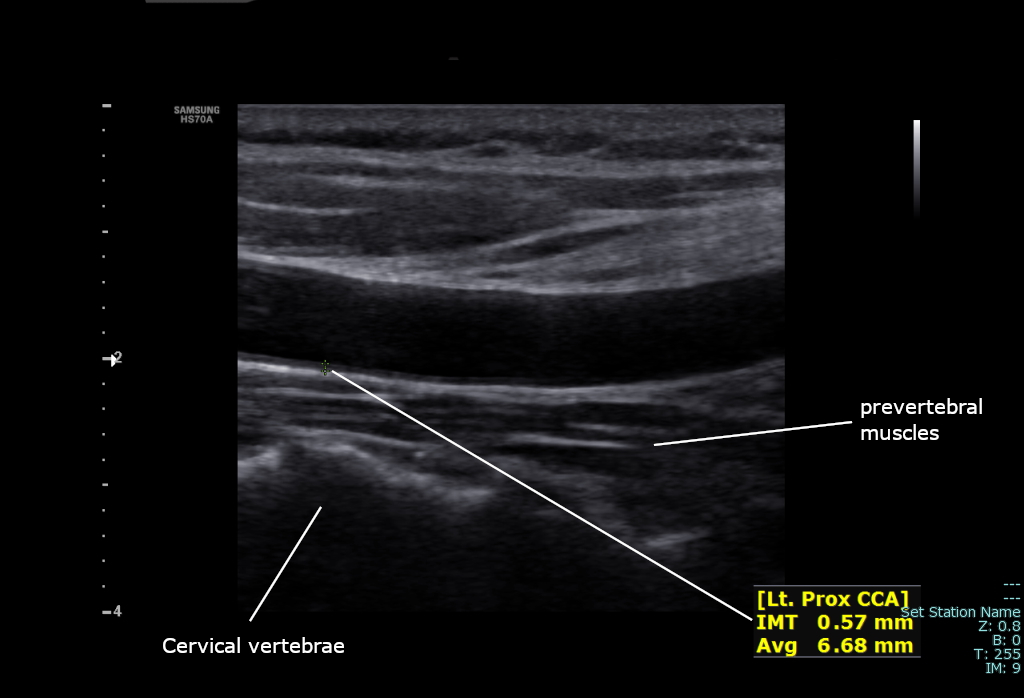

경동맥 벽의 내중막 두께는 임상 이전 죽상경화증의 지표이며, 나이가 들수록, 그리고 미세 입자 대기 오염에 장기간 노출될수록 증가한다.[9]

온목동맥의 상태와 건강은 도플러 초음파, CT 혈관조영술 또는 위상 대비 자기 공명 영상(PC-MRI)을 사용하여 평가한다.

일반적으로 온목동맥의 혈류 속도는 최고 수축기 속도(PSV)와 최종 이완기 속도(EDV)로 측정한다. 20~29세의 정상적인 남성을 대상으로 한 연구에서 평균 PSV는 115cm/sec, EDV는 32cm/sec였다. 80세 이상의 남성의 경우 평균 PSV는 88cm/sec, EDV는 17cm/sec였다.[7]